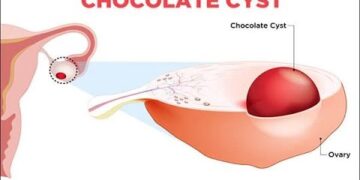

Read moreডা. ফরিদা ইয়াসমিন সুমি গাইনোকোলজিক্যাল সমস্যার মধ্যে অত্যন্ত উল্লেখযোগ্য একটি হলো এন্ডোমেট্রিওসিস। এ রোগটি নারীদের দৈনন্দিন জীবনযাপনের মানের অবনতি ঘটায়...